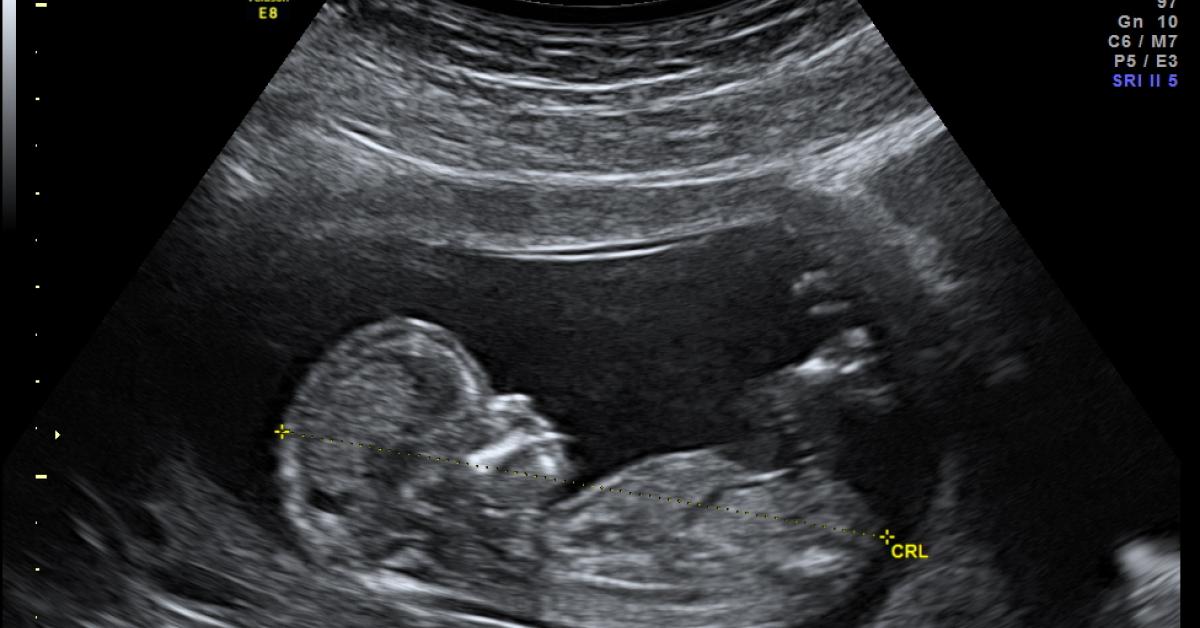

Los recientes avances en la tecnología de secuenciación del ADN y el diagnóstico prenatal han permitido diagnosticar muchas enfermedades genéticas antes del nacimiento. Algunas de estas enfermedades se tratan con terapias de sustitución de proteínas o enzimas después del nacimiento, pero para entonces, algunos de los efectos perjudiciales de la enfermedad se han afianzado. Por lo tanto, la aplicación de terapias mientras el paciente está todavía en el útero tiene el potencial de ser más eficaz para algunas condiciones. El pequeño tamaño del feto permite una dosis terapéutica máxima, y el sistema inmunológico fetal inmaduro puede ser más tolerante a la terapia de reemplazo.

A fin de identificar posibles sistemas de entrega no virales para el ARNm terapéutico, los investigadores crearon una biblioteca de nanopartículas lipídicas, pequeñas partículas de menos de 100 nanómetros de tamaño que entran efectivamente en las células de los receptores fetales de ratones. Cada formulación de nanopartículas lipídicas se utilizó para encapsular el ARNm, que se administró a fetos de ratones.